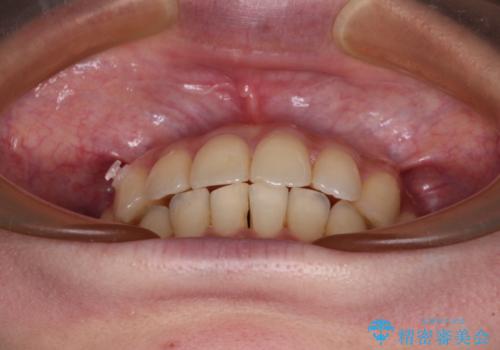

- 前歯のデコボコと強い咬みしめを気にして来院された患者様です。

インビザラインを用いて、前歯の叢生を解消するとともに、ディープバイトを改善していくこととしました。

海外へ転居する予定があったため、1日22時間以上の装着時間をしっかりと守っていただき、予定期間よりも早く、思っていた以上にきれいに仕上げることができました。